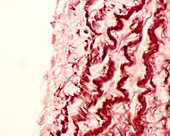

13613450 - Elastic lamellae in aorta, light micrograph

13613436 - Elastic lamellae in aorta, light micrograph